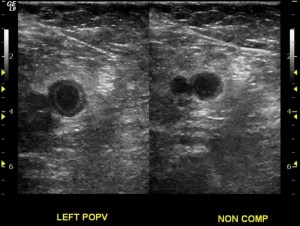

As mentioned above, we should make every effort not to miss a deep vein thrombosis. There are just too many immediate and long term potential consequences that have to be avoided. These include chronic leg pain, chronic venous insufficiency, post phlebitic syndrome, pulmonary embolism and more. These are just too serious to miss. For this reason many patients who present to their doctor with calf pain and/or a swollen calf undergo a leg ultrasound. The ultrasound is designed to look for the clot. Sometimes alternative diagnoses are made. A ruptured Baker’s cyst is one example.